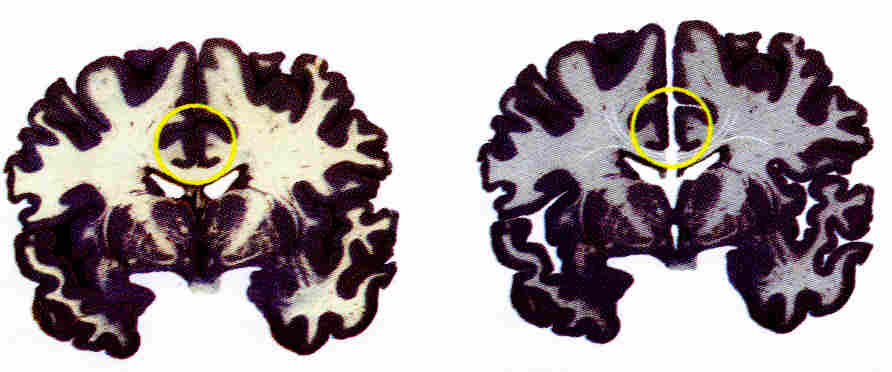

Ageneza spoidła wielkiego

Ageneza spoidła wielkiego.

Okazuje się, że jedna na 4000 osób rodzi się bez spoidła wielkiego! Nazywa się to agenezą spoidła wielkiego (AgCC). Tworzenie się spoidła zachodzi pomiędzy 10-12 tygodniem od poczęcia. Około 1/4 z tych ludzi nie wykazuje żadnych zaburzeń, ale pozostałe 3/4 ma niską inteligencję i różne zaburzenia poznawcze. Ponieważ ich mózgi są od początku pozbawione połączenia pomiędzy półkulami jest dużo czasu by doszło do reorganizacji funkcji, co widać w zwiększonej gęstości połączeń wewnątrz półkul. Chociaż brak jest połączeń strukturalnych to połączenia funkcjonalne wyglądają podobnie jak w przypadku zdrowych dzieci!

Badania przeprowadzono na grupie 20 dzieci z AgCC, porównując wyniki z dziećmi zdrowymi (TDC). Mediana IQ dla dzieci bez spoidła wielkiego to 76, a dzieci typowych 113, jest więc duża różnica, ale też duża wariancja, bo dzieci z AgCC miały IQ pomiędzy 66 a 126, a zdrowe 88-136. Nie znaleziono jednak korelacji pomiędzy IQ a konektomem strukturalnym, co wymaga dokładniejszego zbadania innych anomalii ich mózgów. Jak widać na rysunku poniżej u dzieci z AgCC nie ma połączeń pomiędzy półkulami jednakże połączenia funkcjonalne (czyli synchronizacja sygnałów świadcząca o współpracy) są wyraźnie widoczne. Te rysunki w dość nietypowy sposób pokazują jaka część połączeń z poszczególnych płatów trafia do lewej lub prawej półkuli.

fMRI Ageneza spoidła wielkiego

Ageneza spoidła wielkiego, strukturalne i funkcjonalne.

Rys. powyżej z publikacji Siffredi i inn. (2020). Structural Neuroplastic Responses Preserve Functional Connectivity and Neurobehavioural Outcomes in Children Born Without Corpus Callosum. Cerebral Cortex 31, 1227–1239.

Nie jest to telepatia między półkulami, tylko wynik neuroplastyczności, dzięki której powiększają się spoidła wielkie przednie i tylne. Już wcześniej zauważono wpływ własności tych spoideł na funkcje uwagowe. Zróżnicowanie ludzkich mózgów widoczne w strukturze konektomów i funkcjonalnych konektomach jest większe niż się początkowo wydawało. Na razie (11/2020) nie ma jeszcze badań pokazujących jak to wpływa na procesy świadome, ale jeśli połączenia funkcjonalne są w miarę normalne to jest to całkiem inna sytuacja niż w przypadku osób po komisurotomii.